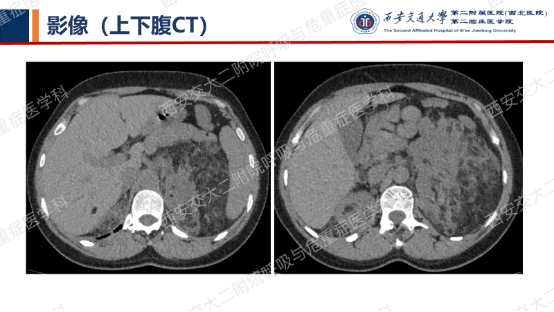

影像学评估发现患者多系统受累(肝脏错构瘤、双肾血管平滑肌脂肪瘤、颅脑多发异常信号结节)。追问病史,患者本人无皮疹、癫痫及智力低下;患者儿子有面部皮脂腺瘤,无癫痫及智力低下,胸腹部CT未见异常,皮肤科已确诊结节性硬化症;患者女儿面容及智力均正常;建议患者进一步行TSC基因检测,结果回报TSC2突变,结节性硬化症诊断明确。